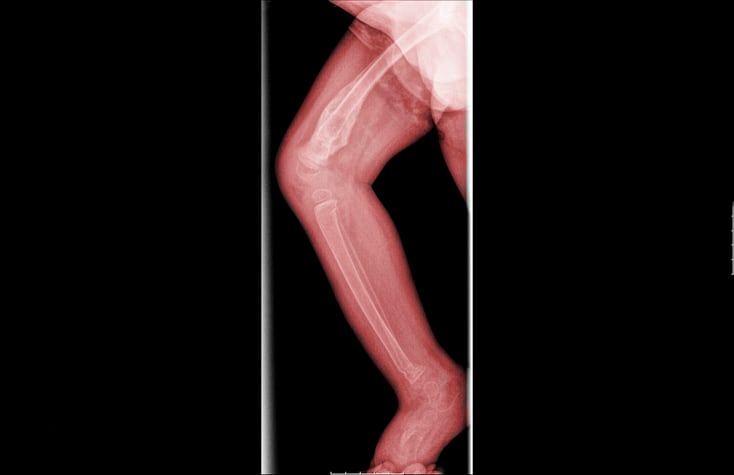

El jurado también vió las radiografías de la pierna rota de Ahziya, las cuales Osbourne dijo que probablemente le causó dolor.